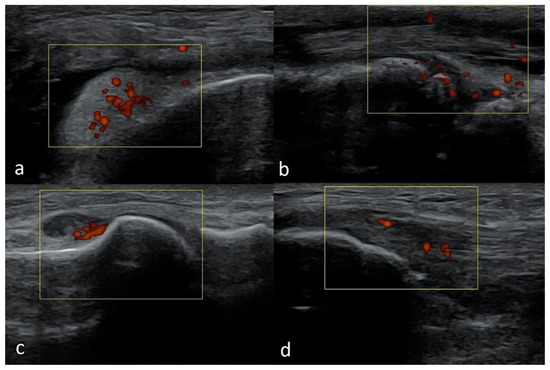

3.2.6. Exudates and Inflammations Affecting Joints

| Joint cavity and recesses | Effusions, synovial thickening, synovial hypervascularity, increased echogenicity of the synovial membrane, indicating chronic inflammation or fibrosis, and presence of loose bodies |

| Bursae | Effusions, synovial thickening, hypervascularity, and loose bodies |